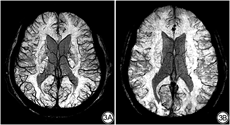

本组数据结果显示,双侧大脑半球SCV的各项量化指标在年龄及受教育年限的分布中差异均无统计学意义(P>0.05)。双侧大脑半球的SCV血管数量在性别分布上差异有统计学意义(右侧P=0.004,左侧P<0.001) (表2),表现为男性的SCV血管数量明显多于女性,且以左侧大脑半球更显著(图3)。